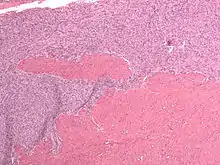

| Micrograph of a low-grade endometrial stromal sarcoma. H&E stain. | |

Low-grade endometrial stromal sarcoma consists of cells resembling normal proliferative phase endometrium, but with infiltration or vascular invasion. These behave less[3] aggressively, sometimes metastasizing, with cancer stage the best predictor of survival. The cells express estrogen/progesterone-receptors.

Microscopy

- Monotonous ovoid cells to spindly cells with minimal cytoplasm.

- Prominent arterioles. Angiolymphatic invasion common.

- Up to 10-15 mitotic figures per 10 HPF in most active areas.

- Tongue-like infiltration between muscle bundles of myometrium.

- May exhibit myxoid, epithelioid and fibrous change.

- May have foam cells or hyalinization in the stroma.